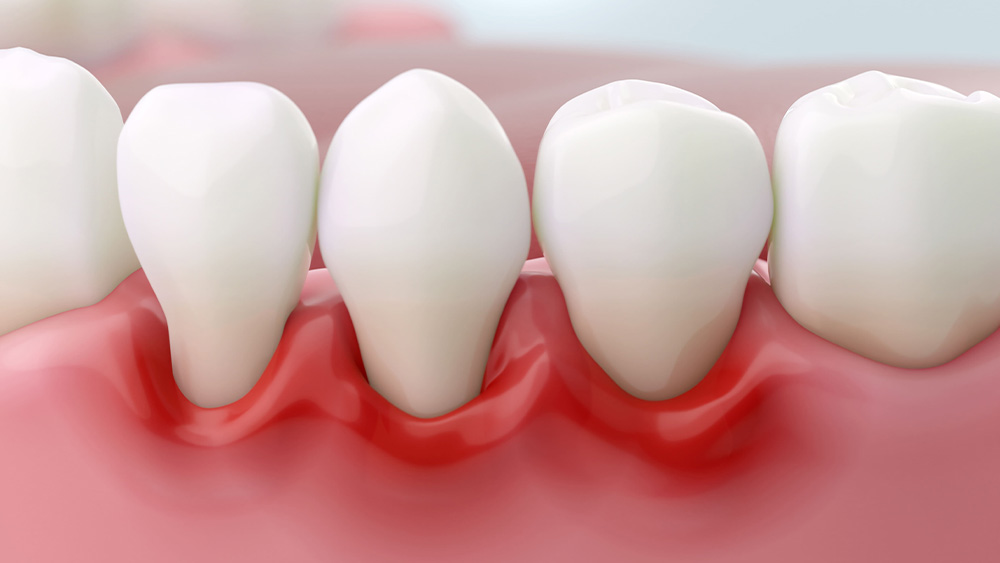

歯周病は、歯を支える骨や歯ぐきが炎症を起こし、徐々に破壊されていく病気です。

歯周病は、歯ぐきや歯を支える骨が細菌によって炎症を起こし、破壊されていく病気です。

初期には自覚症状が少ないことが多いのですが、進行すると歯ぐきからの出血や腫れ、口臭、そして最終的には歯がグラグラして抜け落ちてしまうこともございます。 -